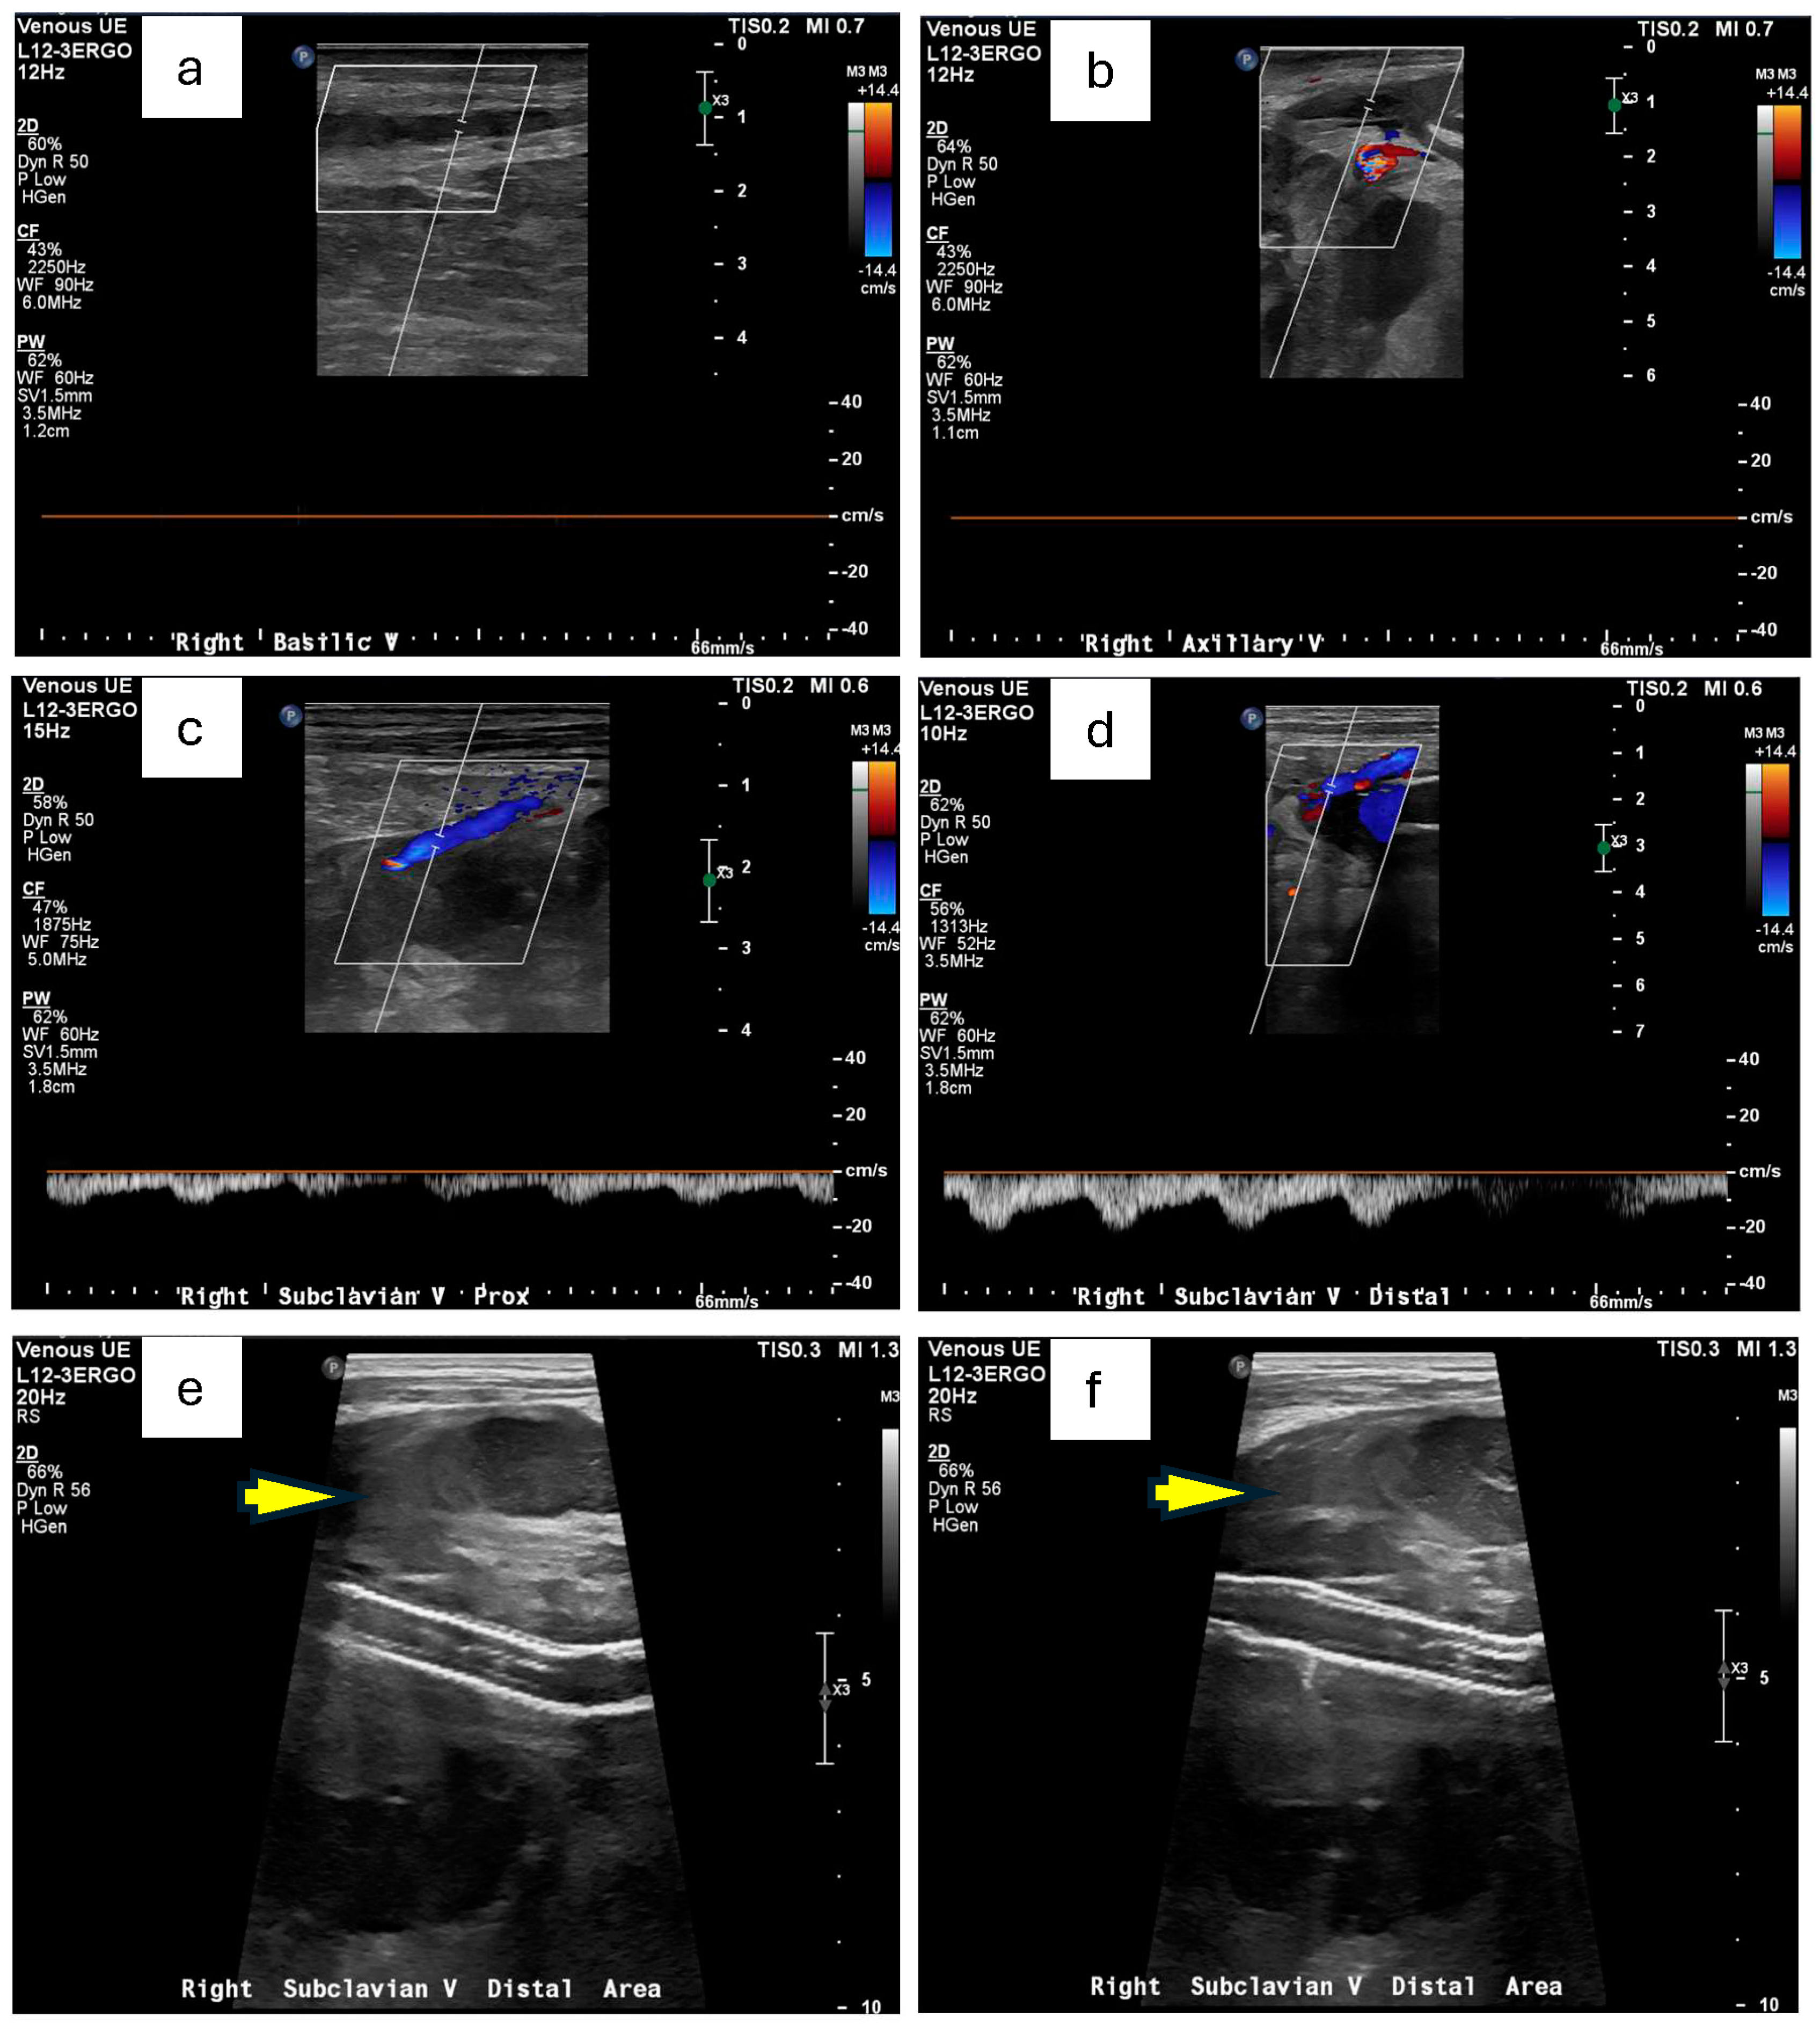

Doppler ultrasound of the right upper extremity confirmed an occlusive deep vein thrombosis of the right axillary vein and a concurrent occlusive superficial thrombosis in the basilic vein (Figure 1a,b). There was also the suggestion of a perivascular hematoma in the region of his subclavian artery stent (Figure 1e,f). Concerned about a possible arterial origin for the hematoma, Vascular Surgery was consulted. A subsequent CT angiogram of the right extremities identified contained ruptures in the right subclavian arteries near the existing stent-grafts, explaining his acute upper extremity swelling and pain (Figure 2a,b). Baseline serum creatinine on admission was approximately 0.84 mg/dL and remained stable (0.71 mg/dL the next day) after this contrast-enhanced imaging, indicating preserved renal function post-CTA (Table 1).

Figure 1. Doppler ultrasound of right arm venous system. (a,b) Occlusive thrombosis of the right axillary vein and right basilic vein is shown by the lack of the Doppler signal compared with other patent veins. (c,d) Examples of patent veins that showed Doppler signal, including the proximal (c) and distal (d) part of the subclavian vein. (e,f) Possibly questionable hematoma in the region of the right subclavian stent as pointed by the yellow arrow.